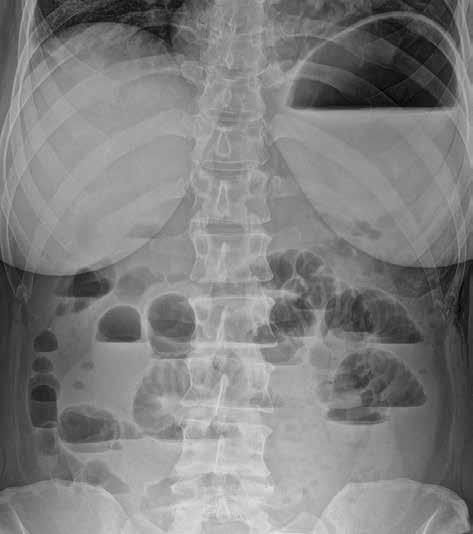

Můžeme provést předozadní snímek vleže na zádech a/nebo zadopřední snímek vestoje v závislosti na indikaci vyšetření. U nemocných ve vážném stavu lze snímkování provádět přímo na lůžku, ovšem za cenu jeho nižší kvality. Prostý snímek břicha vleže na zádech má větší výpovědní hodnotu a standardně i vyšší kvalitu. Přesněji na něm můžeme posoudit šířku lumen tenkého i tlustého střeva. Vzduch tvoří negativní kontrast, který umožní částečně hodnotit šíři střevní stěny i řas. Lépe než u snímku vestoje lze také zhodnotit rozložení plynné náplně střev, a tím i snáze lokalizovat přechodové zóny (obr. 2).

Obr. 2, 3: RTG snímek břicha vleže a vestoje. Ileus tenkého střeva. Vleže je dobře patrná dilatace kliček tenkého střeva nad 3 cm (2). Tenké střevo odlišíme od tlustého přítomností plicae circulares, které obkružují celý obvod lumen střeva. Vstoje vidíme v tenkém střevě hladinky (3).